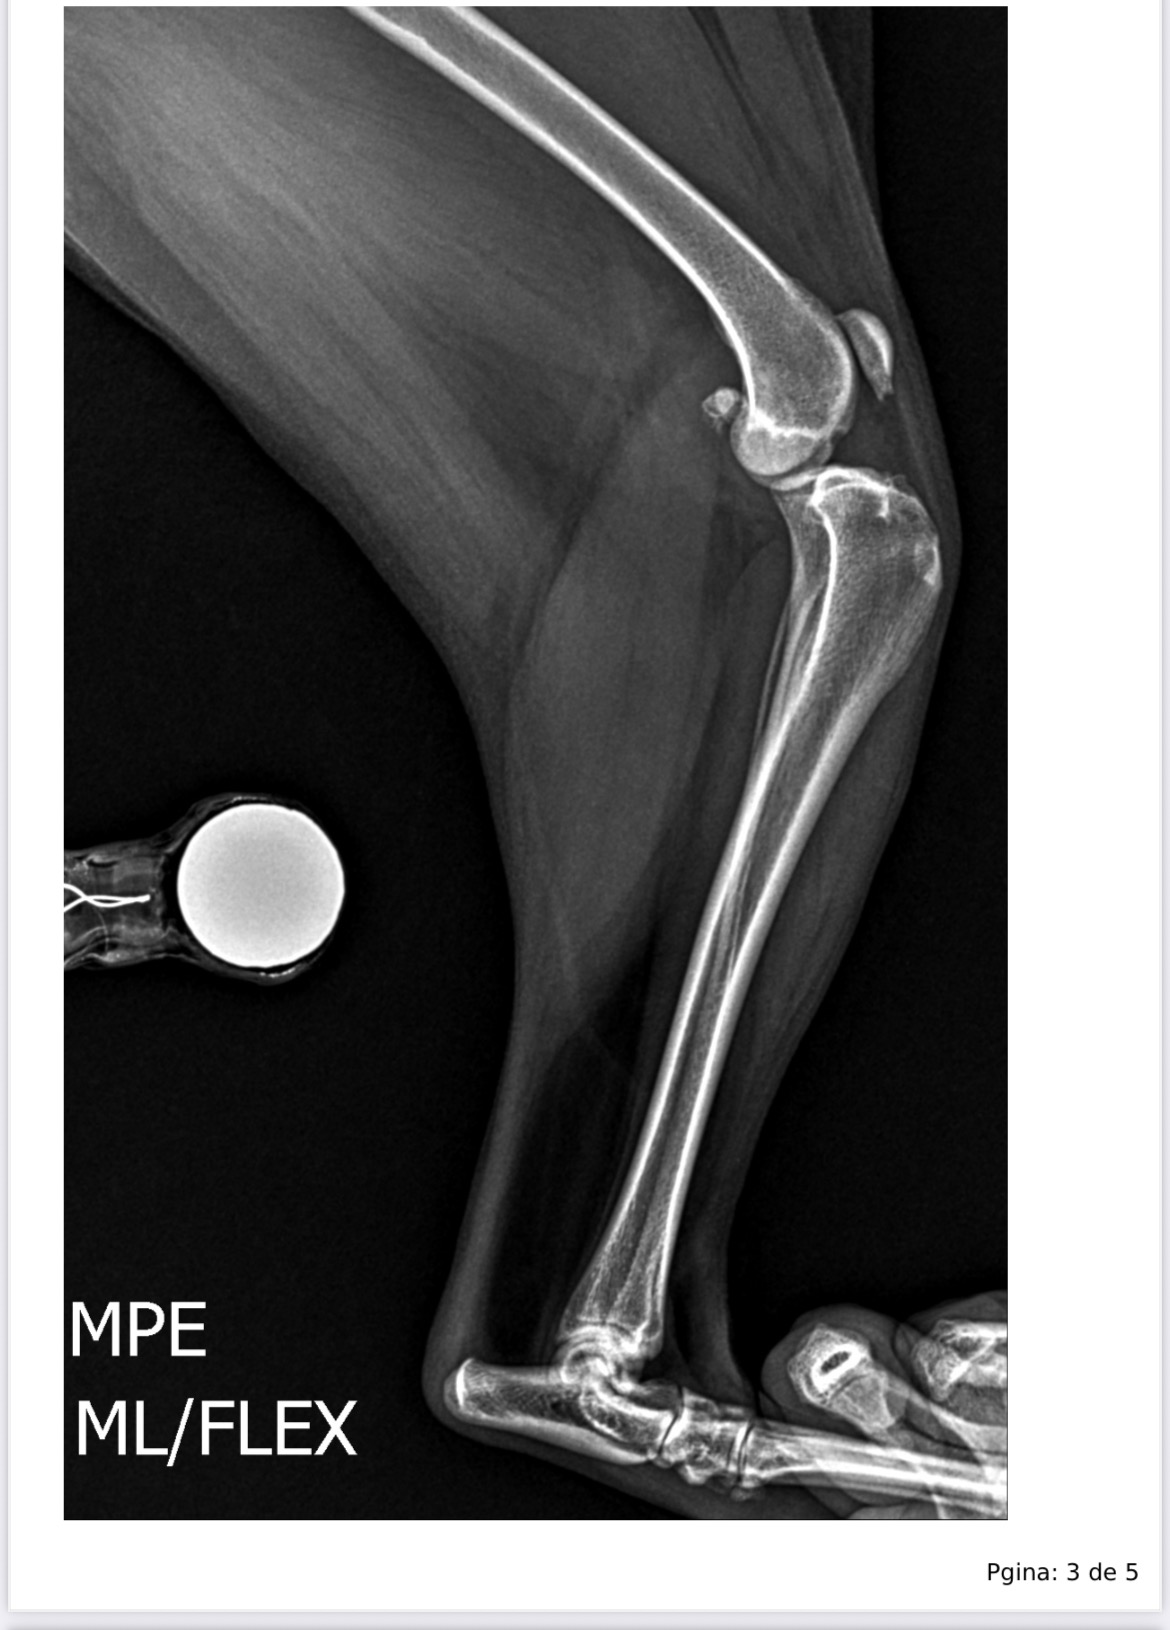

Maia has always been full of energy, with that sweet personality and those eyes that melt anyone’s heart. But now, she is suffering. She has torn the ligaments in both of her knees and dislocated her patella — which means she can no longer walk.